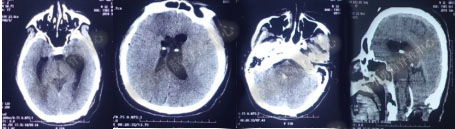

2016年5月9日因“间断性眩晕半月,恶心呕吐一周”以“梗阻性”脑积水,第1次住入北京某企业三级医院神经外科内镜组。2016年5月10日(入院后第2天)行头部MRI(图-1)检查示脑室系统扩张。

图-1:2016年5月10日头部MR

术后7天(2016年5月18日),症状有所缓解,复查头部MRI(图-2)幕上脑室较术前缩小,但是“四脑室仍扩张”,医生认为 “正常”于术后8天(2016年5月19日)出院。

图-2:2016年5月18日头部MRI